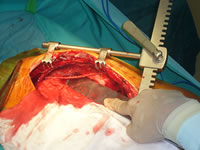

以下、冠動脈バイパス術に関する写真を数枚紹介します。

写真1:内胸動脈を採取しています。

細長いヒモの様に見えるのが内胸動脈です。